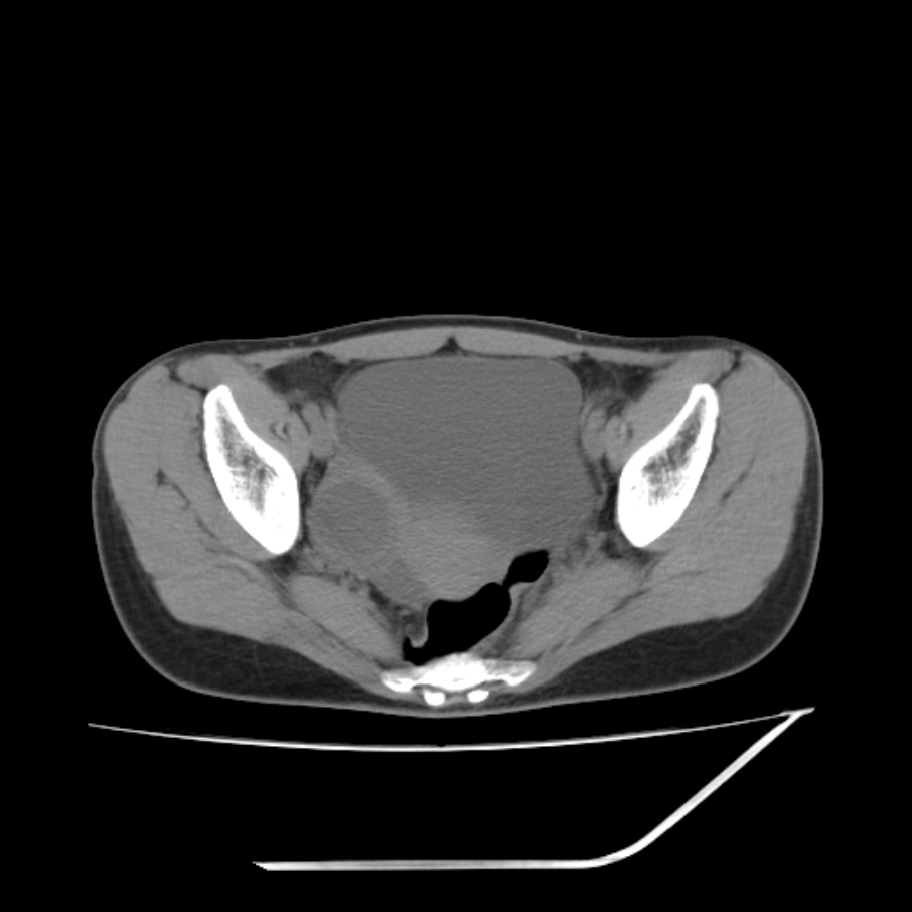

女,25岁。偶尔有右下腹不适感,余无明显异常。(结婚半年),囊壁较厚,是卵巢囊肿吗?

其上一层面见两枚小气泡影,考虑为肠管影可能,不完全除外囊肿

考虑右侧卵巢囊性占位性病变(巧克力囊肿?)。

考虑右侧卵巢囊性病变(巧克力囊肿?)。

右侧卵巢区椭圆形囊性肿物,内壁光滑 无分隔。直肠子宫间隙内有少量积液征象。结合临床考虑卵巢巧克力囊肿,还要问问有没有痛经,本例ct怎么没有灌肠?要是灌肠或前一前口服造影剂,起码可以和肠管区别开

b超示:囊实性占位,畸胎瘤?临床有痛经。

考虑右侧卵巢囊性占位性病变(巧克力囊肿?),盆腔积液有不排除宫外孕可能,请结合临床和b超。